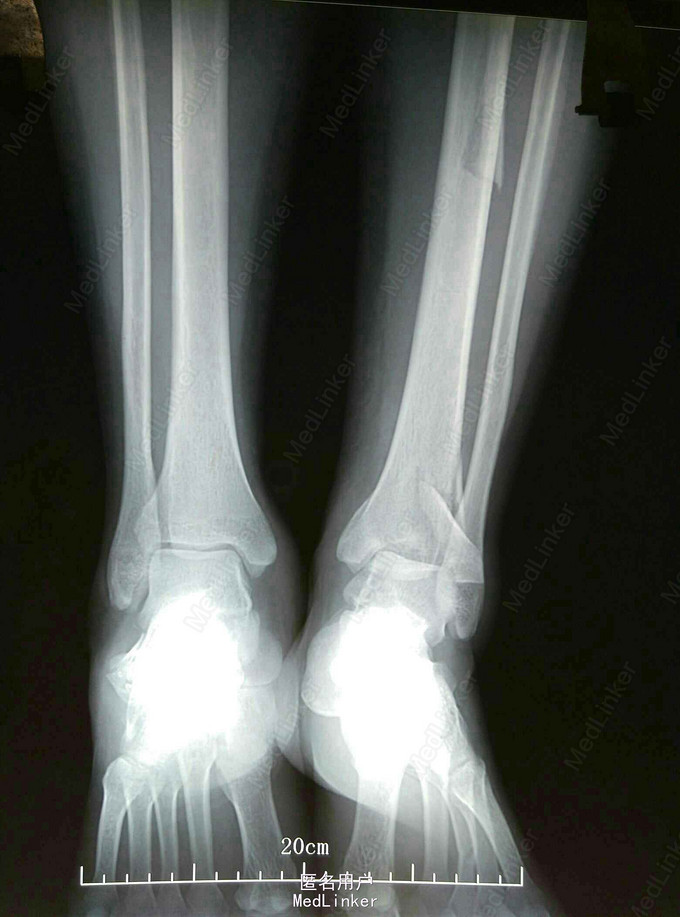

患者女33岁左踝刺痛活动受限5小时 ,患者5小时前擦玻璃时不慎从10米高处坠落伤后来诊。既往:健康。否认肝炎结核等传染病史。

查:左踝肿胀严重,压痛(阳性),左小腿中段压痛。左下肢功能障碍。 足背动脉搏动清,足趾活动良好。 DR:左胫骨pilon骨折。

左胫骨pilon骨折